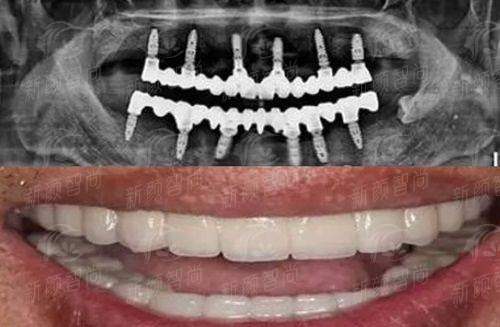

走进深圳市希华爱康健医院口腔科,你会发现这里的诊疗流程和传统医院大不相同。首先,在技术设备上,深圳市希华爱康健医院口腔科全方面引进了国内外精良的数字化诊疗设备。从CBCT全景扫描到口内扫描仪,再到3D数字化导板设计,深圳市希华爱康健医院口腔科真正实现了“精细医疗”。在进行数字化种植牙手术时,医生会利用数字化技术提前模拟手术路径,避开神经血管,大大缩短了手术时间,减轻了患者的术后肿痛感。这种技术优势,是特别多缺乏设备投入的小诊所无法比拟的。